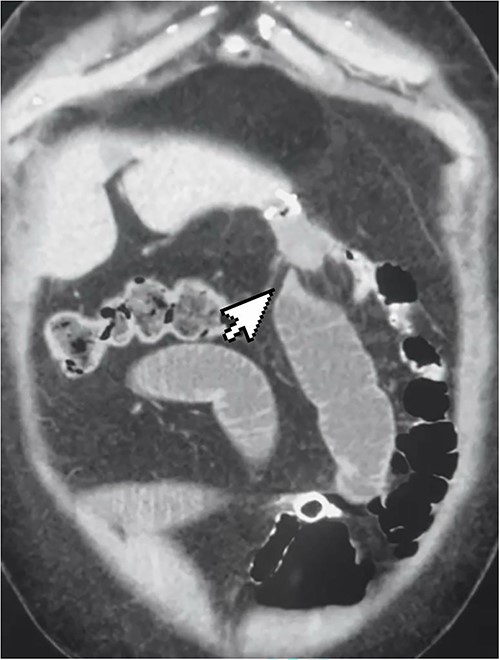

A 50-year-old woman presented to the emergency department complaining of a 3-day history of colicky abdominal pain associated with repeated vomiting and constipation. The patient had a history of OAGB and laparoscopic cholecystectomy 2 months before presentation. During the examination, she was conscious and had normal vital signs. An abdominal examination revealed mild distention and tenderness in the epigastric region. An x-ray of the abdomen showed minimal air-fluid levels. Laboratory tests were unremarkable, except for lipase 135 and C-reactive protein 54. The patient consented to an abdominal computer tomography (CT) scan with intravenous and oral contrast. The CT scan revealed a high-grade obstruction at the jejunum afferent loop with a maximum diameter of 4 cm. No fluid collection, mural thickening, oedema, or fat stranding were detected (Fig. 1). A nasogastric tube was inserted, but no relief or progression was seen in the patient’s situation. The possibility of surgery was raised to the patient, and after mutual agreement, anaesthesiology assessed her for diagnostic laparoscopy.

CT scan showing high-grade small bowel obstruction and twisting at the gastro-jejunal anastomosis.